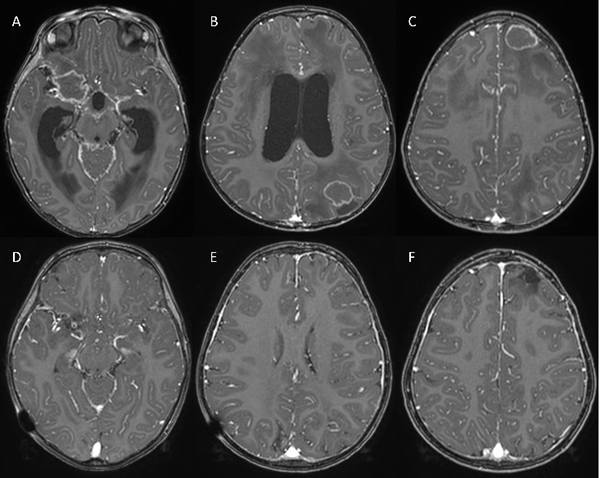

Actualmente, la paciente cumple un año de tratamiento antituberculoso, observándose franca disminución del tamaño de las lesiones (Figura 2). Al examen físico, la paciente no presenta déficit neurológico, con recuperación completa del III par craneal.

Figura 2: Se observan RMN con contraste de ingreso (A, B y C) y al año de la cirugía y tratamiento antibiótico (D, E y F).